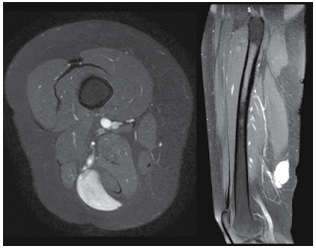

Uma paciente de 36 anos vem ao ambulatório de cirurgia vascular por apresentar nodulação em face posterior de coxa, depressível, pouco dolorosa e relacionada a ortostase. Como propedêutica complementar, a paciente já traz uma angioressonância com imagens de interesse apresentadas na figura a seguir:

Enunciado 4377372-1

(Arquivo pessoal; imagem usada com autorização)

A partir da análise das imagens, assinale a alternativa que corresponde ao diagnóstico em questão.